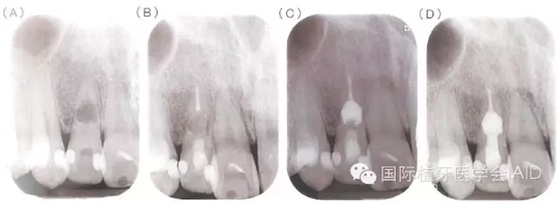

牙根內(nèi)吸收若是早期發(fā)現(xiàn),在未與牙周組織相通的情況下治療步驟相對(duì)單純以徹底去除導(dǎo)致牙髓腔內(nèi)感染與內(nèi)吸收窩洞內(nèi)的肉芽組織為首要目標(biāo),可運(yùn)用機(jī)械性的清創(chuàng)配合次氯酸鈉溶液與超聲波器械的沖洗,加強(qiáng)清創(chuàng)效果,之后于根管內(nèi)放置氫氧化鈣至少1~2周,在無(wú)臨床癥狀下,便能以古塔膠熱塑性封填系統(tǒng)(warmgutta percha technique)或是三氧礦化物(MTA,mineral trioxide aggregate)進(jìn)行根管封填;但若此內(nèi)吸收為與外界相通的牙根吸收病灶,由于MTA具有良好的密封能力(sealingability)及生物兼容性(biocompatibility)會(huì)是更恰當(dāng)?shù)倪x擇(下圖)。

(A)31歲男性因牙位12顏色改變求診,該牙無(wú)臨床癥狀,但X光檢查發(fā)現(xiàn)在牙根中段有一個(gè)約4.5*5mm的橢圓形呈放射線透性影像,檢查時(shí)牙髓組織已無(wú)活性反應(yīng)并診斷為牙根內(nèi)吸收。(B)于顯微鏡下進(jìn)行根管治療,根管內(nèi)有出血現(xiàn)象且有肉芽組織沾粘于管壁,懷疑病灶與根管外相通,移除發(fā)炎組織后進(jìn)行根管清創(chuàng)搭配超音波器械沖洗,并放置氫氧化鈣。根管封填分兩部份進(jìn)行,先以古塔膠填充填下半部根管;(C)以MTA充填于吸收窩洞,確認(rèn)MTA硬化后,以復(fù)合樹脂填補(bǔ)根管開口;(D)根管治療完成后一年的追蹤,該牙無(wú)癥狀且周邊組織愈合良好。